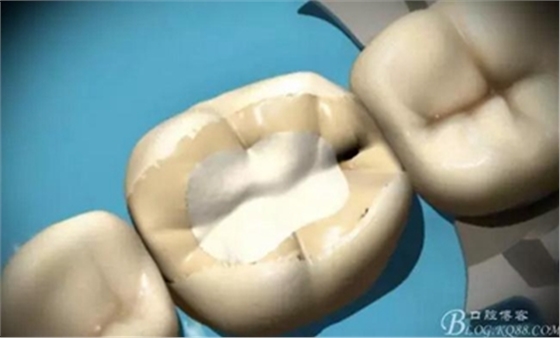

綠標平頭錐形金剛砂牙合面牙體預(yù)備

預(yù)備要求

綠標平頭錐形金剛砂鄰面牙體預(yù)備

釉質(zhì)鑿去飛邊

制作完成

高嵌體

高嵌體病例圖片